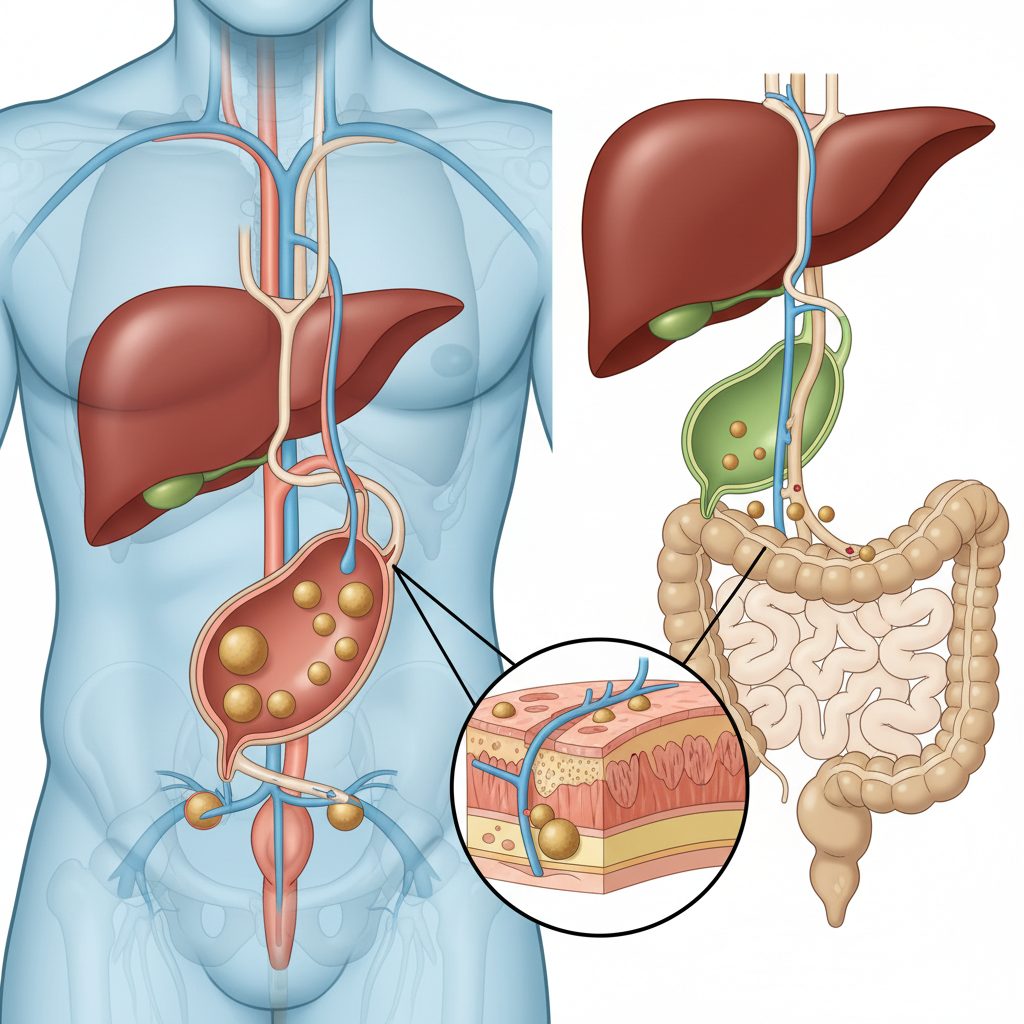

Safra kesesi, karaciğerin ürettiği safrayı depolayan ve özellikle yağlı yiyecekler tüketildiğinde safrayı ince bağırsağa gönderen küçük bir organdır. Safra; yağların sindirimine yardımcı olan safra asitleri, kolesterol, bilirubin ve bazı tuzları içerir. Bu bileşenlerin dengesi bozulduğunda safra içinde kristaller oluşabilir ve zamanla bu kristaller birleşerek safra kesesi taşları haline gelebilir.

Bazı kişilerde taşlar uzun süre belirti vermez (asemptomatik safra taşı). Ancak taş safra kesesi çıkışını tıkadığında “safra koliği” denilen ağrı atakları başlayabilir. Taşın safra kanalına düşmesi ise daha ciddi tablolara (ör. koledok taşı, pankreatit, kolanjit) zemin hazırlayabilir. Bu nedenle “taş var ama şikâyet yok” ile “taş var ve kanal tıkandı” durumlarını ayırmak önemlidir.